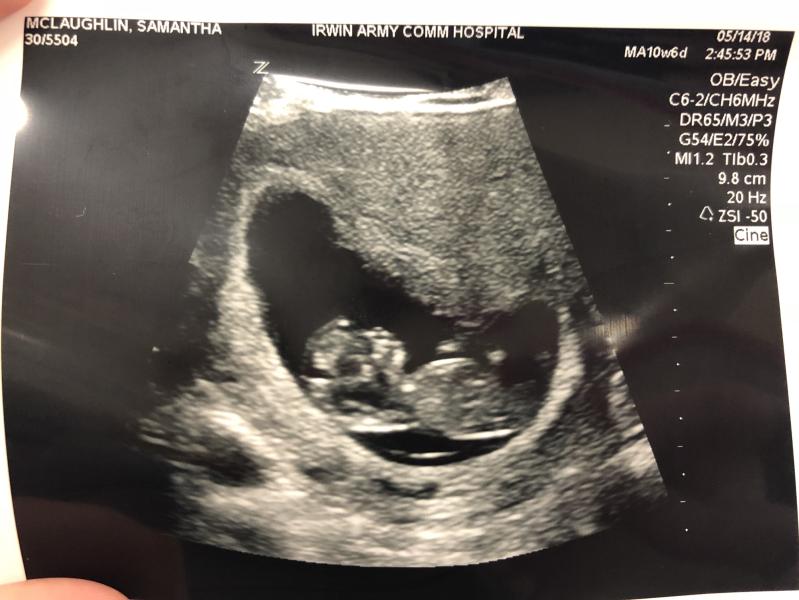

First ultrasound! Baby measured 11wks. I’m 10wks 6days. Keeping due date of 12/4!!

@firsttimepregomommy, I was super nervous for this ultrasound. Huge sigh of relief once I saw that HB! It doesn’t help that when I went to verify my pregnancy (I was 9wks) I did a urine test and the lab told me it was negative (mind you. I’d already seen a baby and hb at 7wks in the er for a super quick scan cuz I was spotting) so of course every scenario was playing in my head.

@firsttimepregomommy, it’s such a relief isn’t it!? Mine was 171 today!